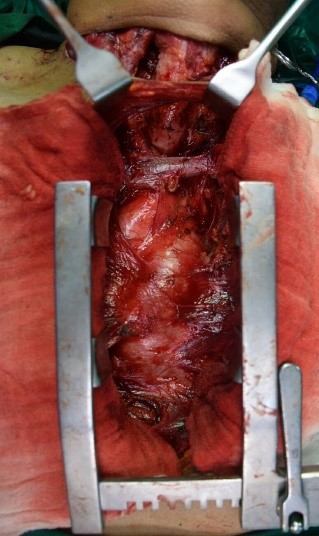

Right Upper Lobe Sleeve Bronchial Resection

Lung cancer surgery as Bronchus sleeve resection